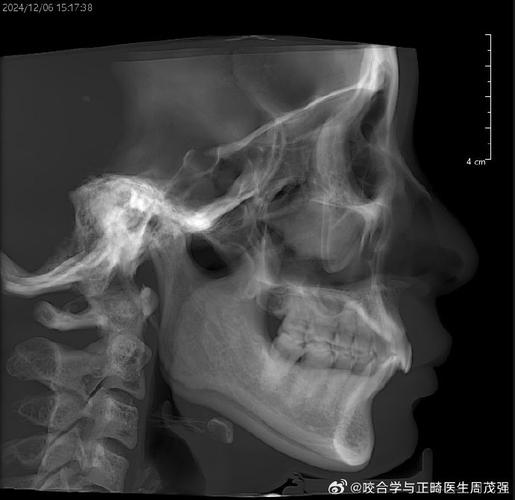

预防正畸后TMD的关键在于规范治疗和全程监控,正畸前需进行全面评估,包括关节触诊、咬合分析、必要时拍摄关节X线片或进行磁共振检查,排除潜在关节问题,治疗中应遵循“轻力矫治”原则,避免急功近利,定期复查调整方案,确保牙齿移动与肌肉、关节协调适应,对于存在TMD倾向的患者,可设计分阶段治疗,先通过咬合板或肌肉训练稳定关节,再进行牙齿矫正,治疗后需注意咬合适应,避免过早进食过硬食物,同时纠正不良习惯(如单侧咀嚼、托腮)。